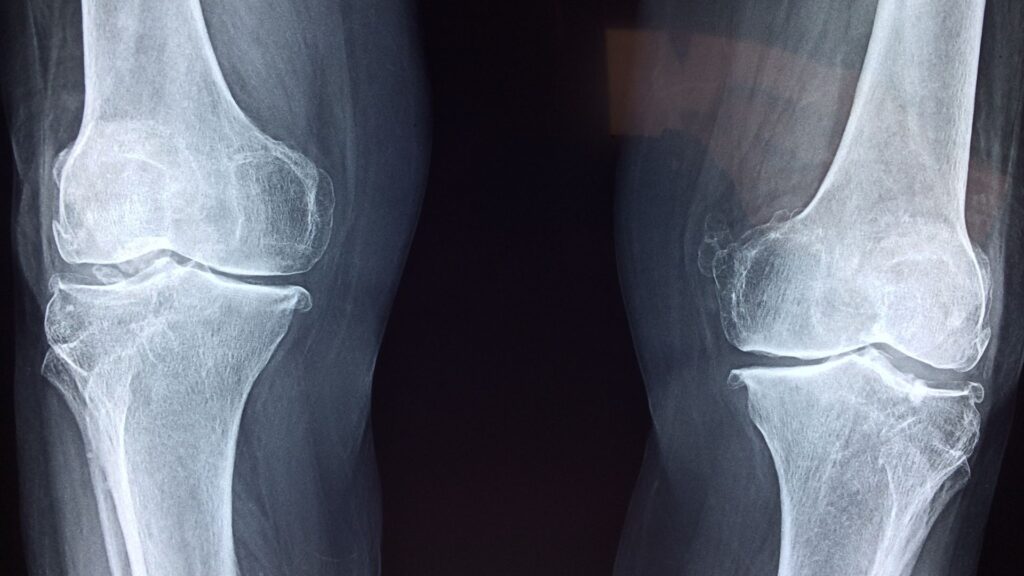

An ACL tear is one of the most common knee injuries, especially for active individuals. This ligament is crucial for knee stability, and an injury can significantly impact mobility and quality of life. As dedicated knee specialists, we emphasize the importance of early and accurate diagnosis to map out the most effective treatment plan.

When dealing with complex joint issues, seeking specialized care is vital. An orthopedic knee doctor has the focused training to diagnose the full extent of the injury. As a premier orthopedic specialist in Austin, TX, our team uses advanced diagnostics to ensure we provide a comprehensive and accurate treatment strategy for every patient.

Beyond ACL reconstruction, our institute offers a full spectrum of knee services. From managing arthritis to performing complex ligament repairs, our commitment is to restore function and get our patients back to their active lives. We believe in a patient-first approach, tailoring every treatment plan to the individual’s unique needs and goals.